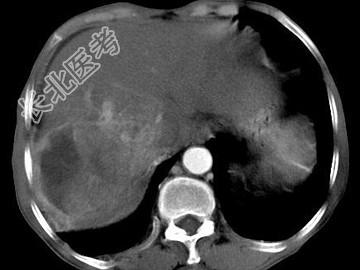

- 单项选择题女,40岁, 有口服避孕药史,肝区疼痛、腹部包块, AFP阴性,CT扫描如图, 最可能的诊断是

A、肝细胞腺瘤

B、肝再生结节

C、结节性肝癌

D、肝右叶巨块型肝癌

E、肝黄色肉芽肿